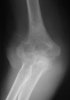

X-ray : 경과 골절(Transcondylar fracture)

상과 부위에서 발생하여 주두와(olecranon fossa)에 이르는 골절입니다.

손상 기전이나 치료 원칙은 과상부 골절과 동일하나 골절이 관절낭 내에 위치하므로 과다한 가골 형성은 운동 범위의 제한을 초래합니다.